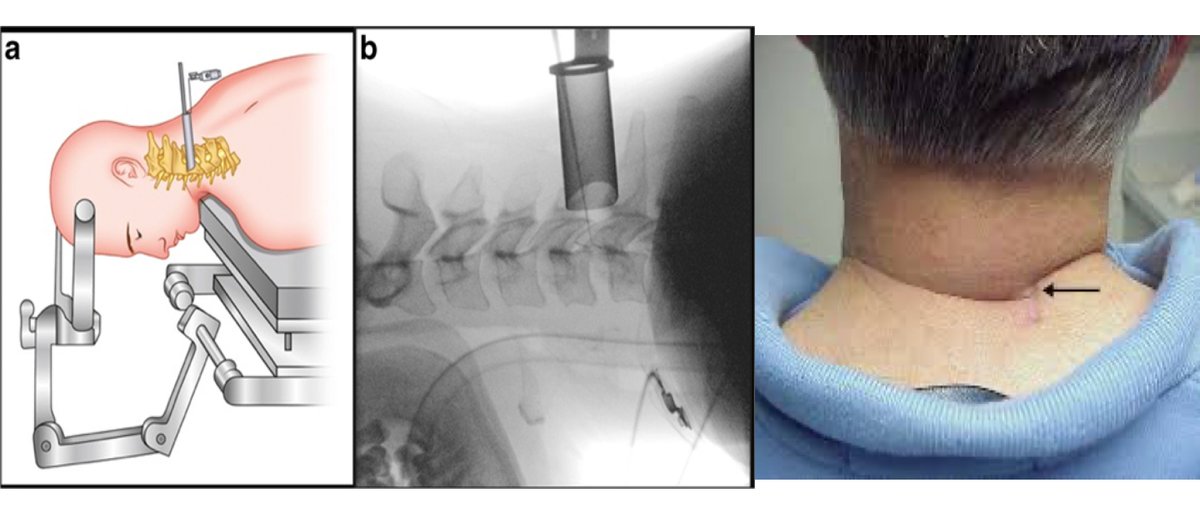

🔟MIS cervical foraminotomy تحرير الأعصاب العنقية

المشاكل المتعلقة بالانزلاق الغضروفي الضاغط على الأعصاب العنقية تعالج غالبًا عن طريق جرح في أمام الرقبة، ولكن هناك بعض الحالات تحتاج إلى تحرير العصب من الخلف، ومن التقنيات الحديثة هو استخدام تقنية الأنبوب من خلال جرح صغير في خلف

1⃣1⃣

الرقبة لتوسيع القناة العصبية وتحرير العصب.